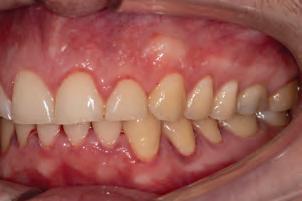

A 77-year-old Caucasian patient presented to the dental clinic after five years without dental care. The clinical findings showed significant bone loss, chronic periodontitis, and loss of some teeth that stabilized the occlusion. The patient reported cold sensitivity in tooth #46, especially when ingesting liquids.

Periapical X-ray confirmed the findings of the clinical examination and root caries was also detected in the distal root of tooth #46, which answered positively to the sensitivity test (Fig.1-2).

The treatment plan began with a focus on returning the patient to adequate periodontal health. In a subsequent session, with improved condition of the periodontium, the restoration of tooth #46 was performed. Under block anesthesia of right inferior alveolar nerve and rubber dam isolation, the amalgam restoration was completely removed and access to the caries cavity obtained (Fig. 3-5). Despite the proximity to the pulp tissue, no exposure occurred, and the class II cavity was fully restored with Biodentine™ (Fig. 6-8).

At two months’ follow-up, no symptoms were reported, no periapical lesion was observed radiographically, and the clinical examination showed normal vitality (Fig. 9-10). Thus, it was decided to perform the definitive restoration, leaving Biodentine™ as the definitive base.

The Biodentine™ material was partially removed and a resin composite filling placed over it (Fig. 11). Selective etching of enamel was done, followed by the application

Pedro Alexandre1

of an adhesive system (Palfique Bond®, Tokuyama) (Fig. 1213). After light-curing, the matrix system (SeptoMatrix, Septodont) was set and a large matrix with a soft ring was used for a better contour and proximal contact point (Fig. 14). The restoration was started in the distal portion, changing the class II cavity into a class I cavity (Fig. 15). Finally, the occlusal face was completed using Palfique LX5® (Tokuyama) composite (Fig. 16). After light-curing, glycerin gel was applied to allow better photo-activation of the surface layer. The restoration was then finished and polished, before removing the rubber dam and checking occlusion (Fig. 17).

Fig. 1: Initial clinical situation.

Fig. 4: Septomatrix in position.

Fig. 2: Initial X-ray.

Fig. 5: Cavity deep.

Fig. 3: Class II cavity prepared.

Fig. 6: Biodentine™ applied in a Bio Bulk-Fill approach.